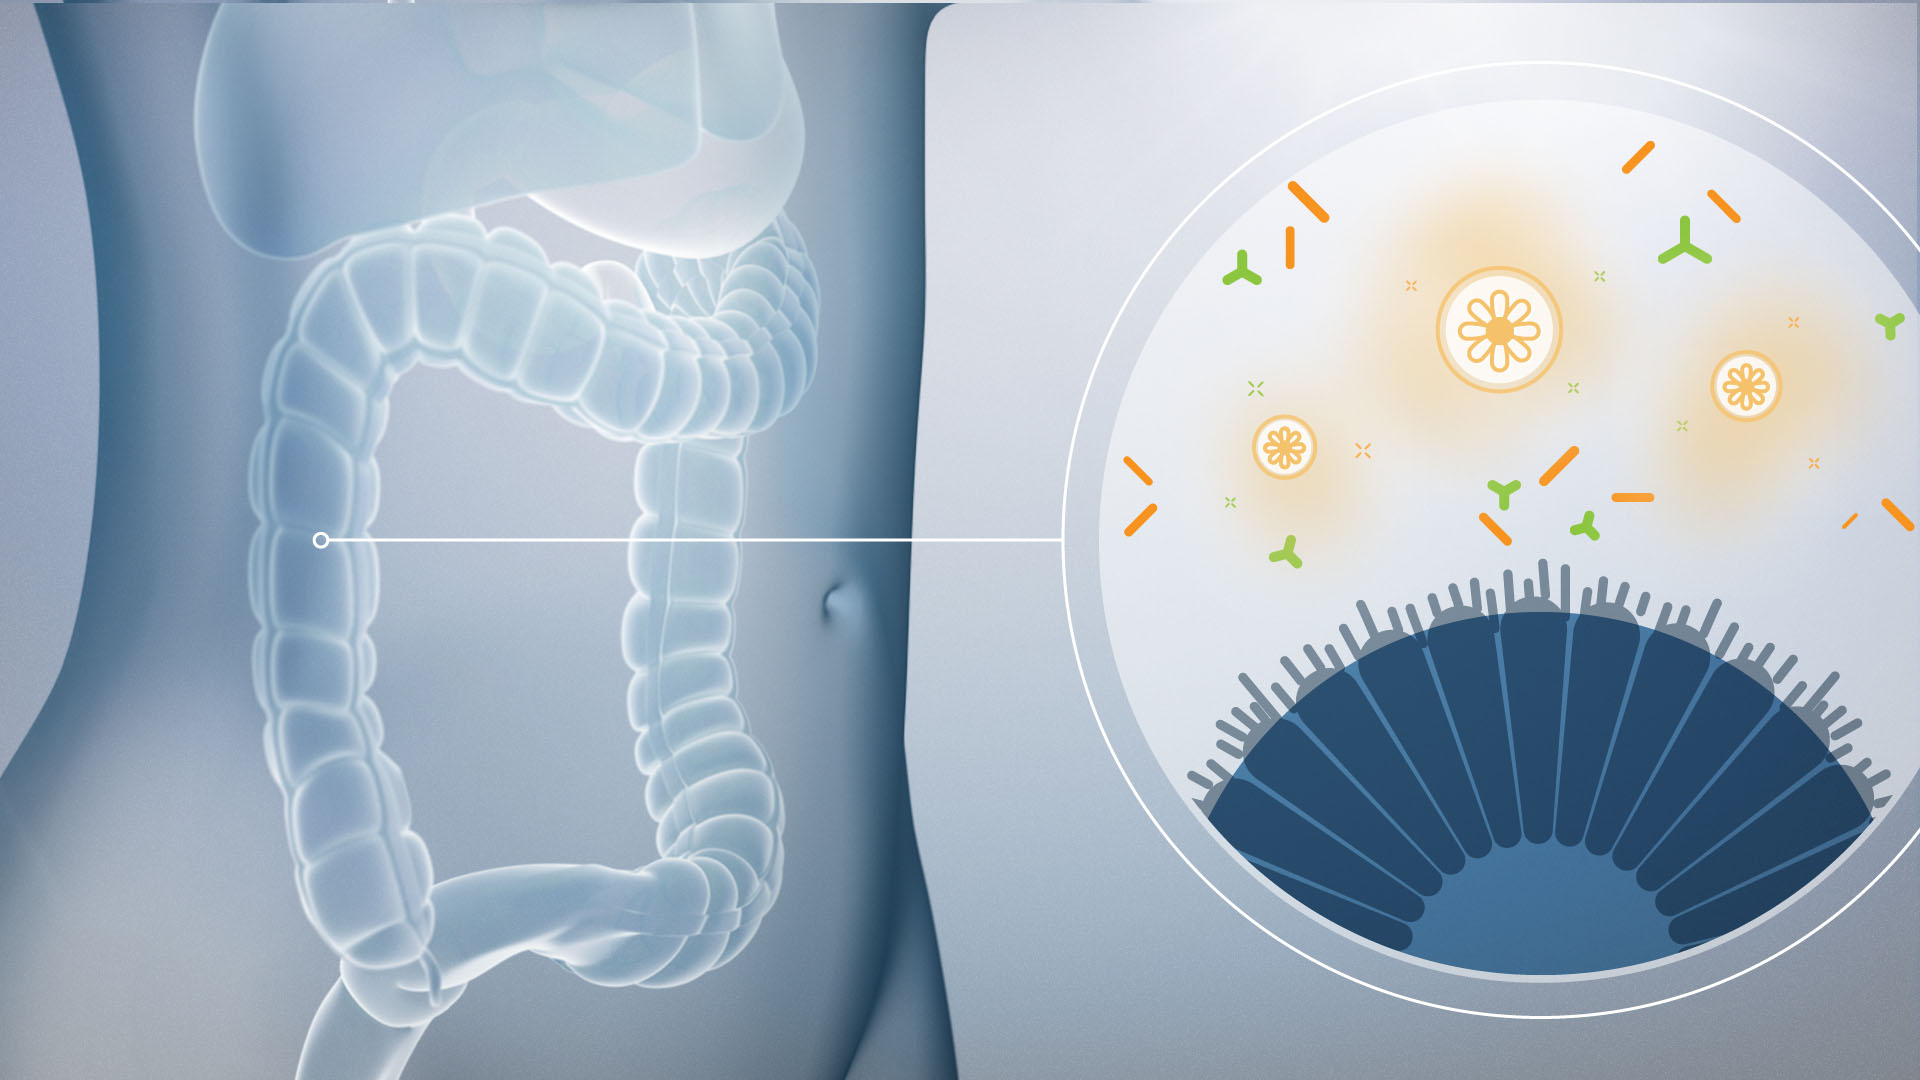

3D-WORKS

Manchmal muss es einfach 3D sein. Auch wenn sich in unseren 2D Animationen mehr 3D versteckt als man denkt, sind unsere realistischen Renderings immer etwas Besonderes. Speziell auf dem Gebiet der Medizin haben wir schon viele Projekte in 3D realisiert. Auch wenn wir davon hier nur wenig öffentlich zeigen dürfen.

COMPOSITING

Ja, Grafiken und 3D Animationen mit realem Material zu verschmelzen, löst immer wieder eine Faszination in uns aus. Auch weil Realfilm-Produktionen einfach Spaß machen!